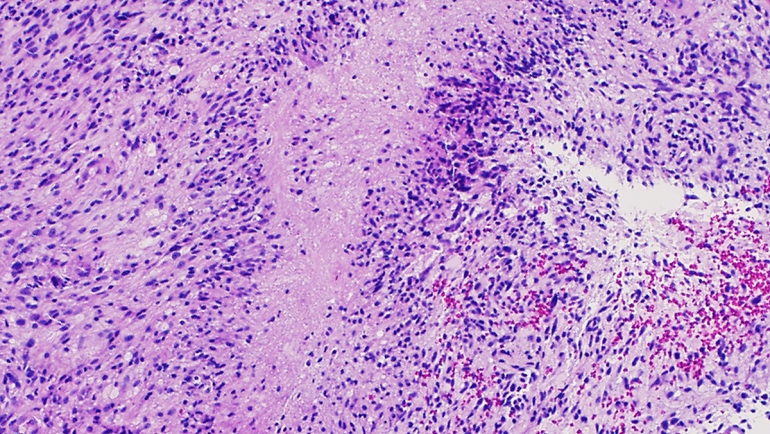

Researchers Unlock Secret of Deadly Brain Cancer’s “Immortality”

glioblastoma